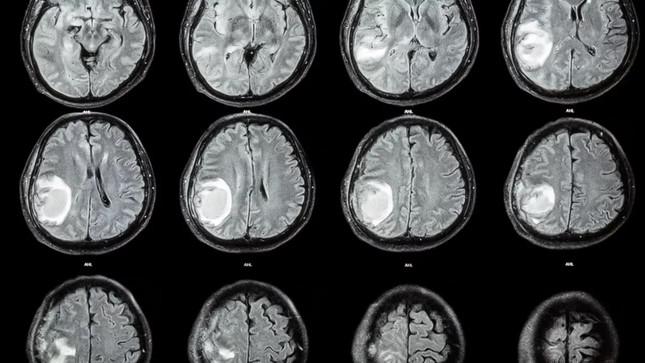

Quét CT trên nền đen cho thấy một khối màu trắng sáng trong não của đứa trẻ 1 tuổi

Quét não đầu của đứa trẻ 1 tuổi cho thấy thai nhi có cột sống và hai xương chân (xương đùi và xương chày), và thai nhi dị tật bị nứt đốt sống, một tình trạng trong đó một phần của tủy sống bị lộ ra ngoài do một vấn đề trong quá trình phát triển. Sau khi được lấy ra, khối bào thai cũng được xác định là có "chồi chi trên và giống ngón tay".